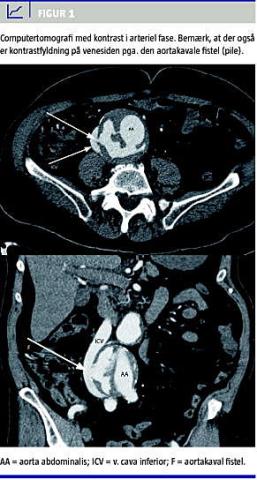

En 84-årig mand, der havde velreguleret, lettere hypertension, men i øvrigt i det væsentligste var rask, blev indlagt akut under diagnosen obs. akut koronart syndrom, da han havde haft kvalme og svære smerter i thorax og epigastriet med udstråling til ryggen. Ved ankomsten var patienten upåvirket, men to timer senere recidiverede symptomerne i svær grad, og parallelt hermed blev han akut påvirket, klamtsvedende, takypnøisk og hæmodynamisk ustabil med blodtryk på 70/40 mmHg. En elektrokardiogrammåling viste nu takykardi og ST-depression i afledninger V5-6. En akut bedside -ekkokardiografi viste normale forhold. Akut computertomografi af thorax og abdomen viste et 8 × 10 cm stort infrarenalt AAA. Dette havde en 10 mm stor fistel imellem aorta abdominalis og vena cava inferior. Det drejede om en arterie-venøs fistel med retrograd fyldning af det venøse system (Figur 1 ).